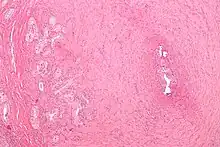

| Micrograph of vasitis nodosa (left of image). H&E stain. | |

Vasitis nodosa is a complication experienced in approximately 66% of men who undergo vasectomy.[1] It is a benign nodular thickening of the vas deferens, in which small offshoots proliferate, infiltrating surrounding tissue.[2] It can be mistaken for low-grade adenocarcinoma by pathologists,[3] and is implicated in late vasectomy failure.[2]